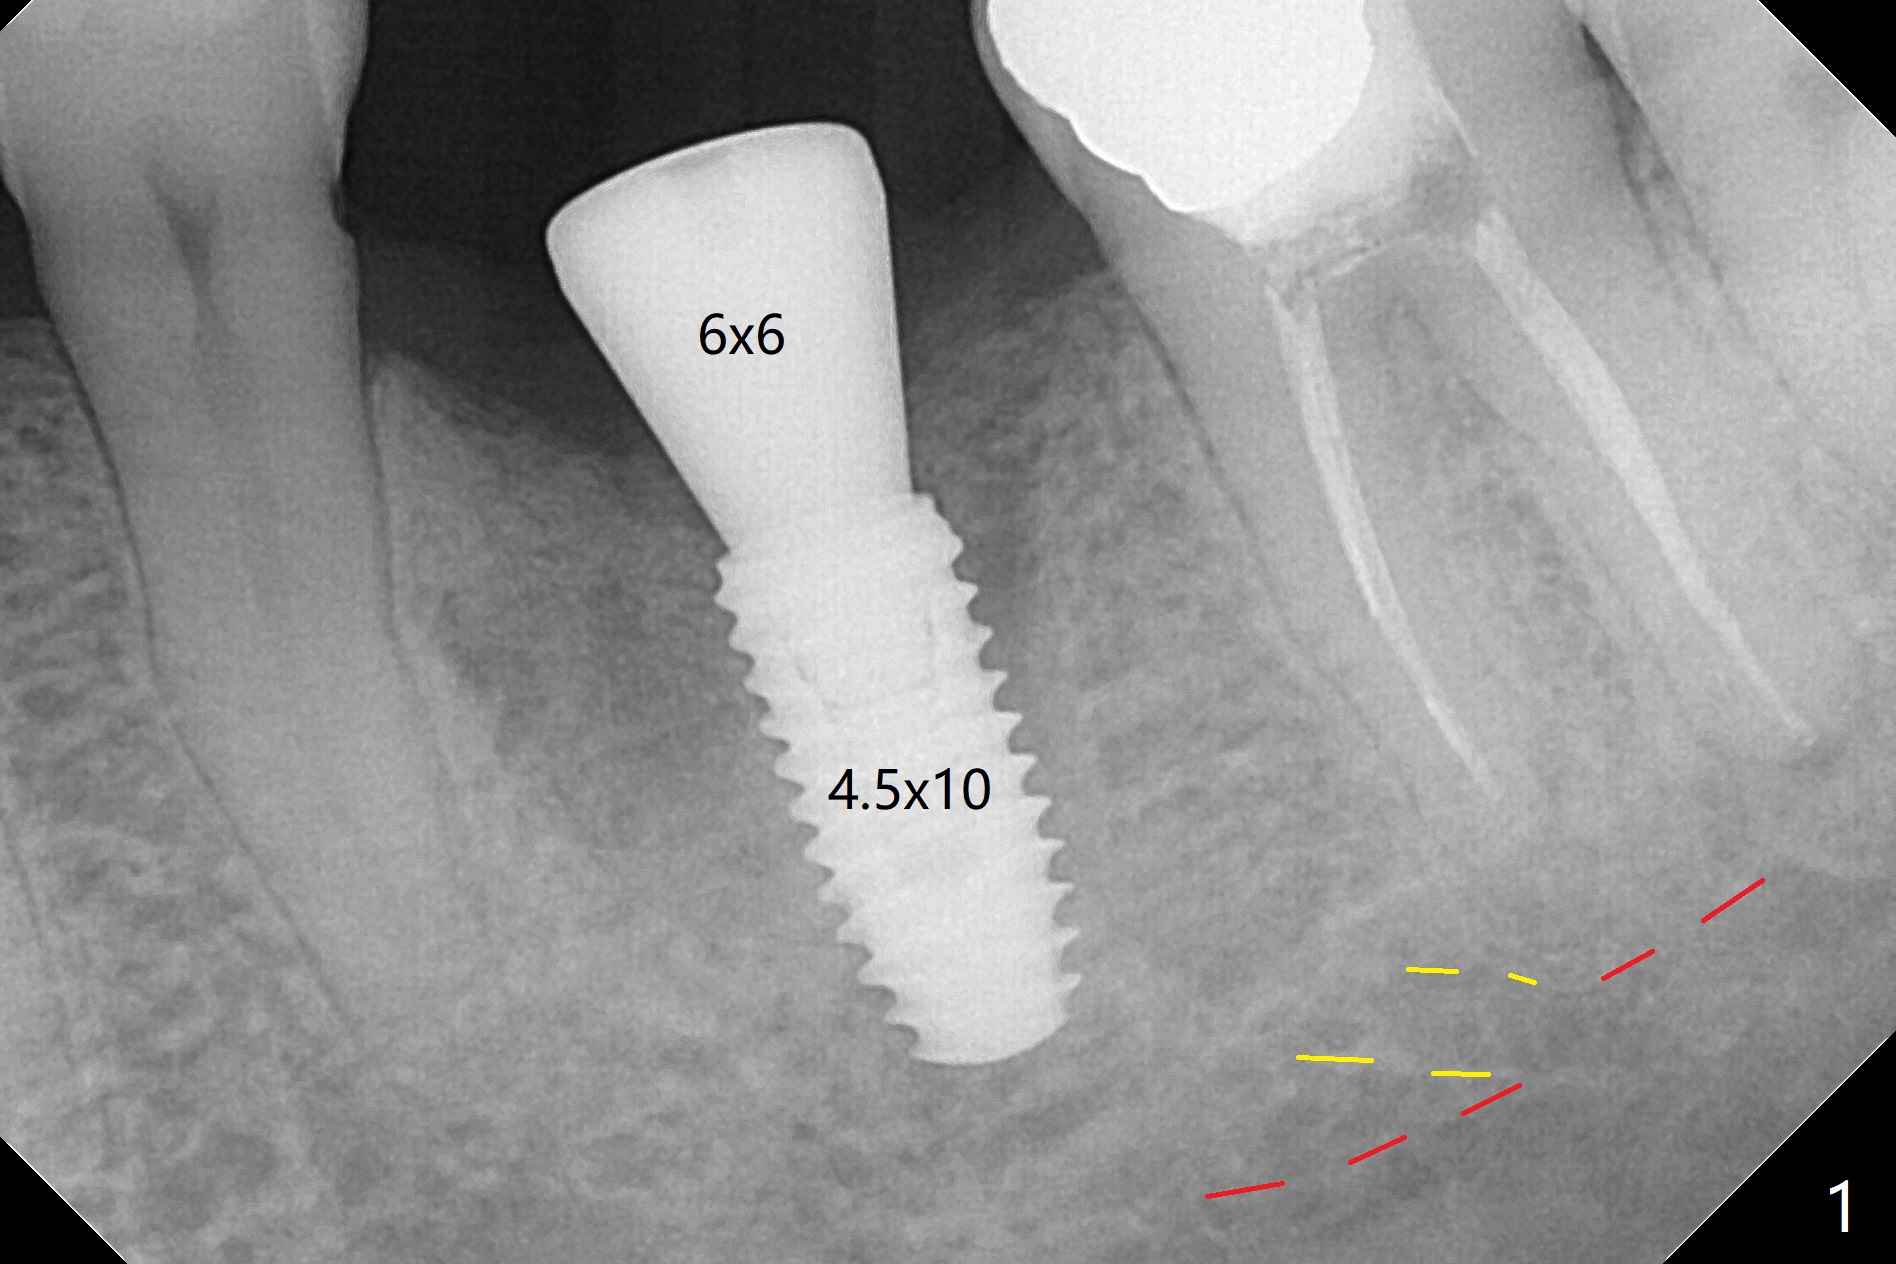

Due to low bone density associated with no bone graft after extraction and possible accessory nerve, osteotomy at #19 is underprep in diameter (3.5 vs. 4.0x8.5 mm), but overprep finally in length (3.5x10 mm) with 1 ampule of Lidocaine. Insertion torque associated with 4.0 and 4.5 mm cortical taps and 4.5x10 mm implant (Fig.1) is between 30-55 Ncm. Since the implant is covered by buccal and lingual bone associated with deep placement, no bone graft is conducted. The lingual gingiva has minor laceration near the access. Periodontal dressing is applied. It remains in place a week postop due to retention associated with the healing abutment (Fig.2 *). A long abutment is placed for restoration 4 months postop (Fig.3), increasing the chance of abutment screw loosening (as compared to immediate implant) if the abutment is incompletely seated.